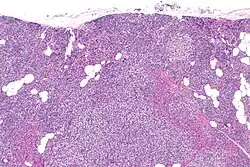

La hiperplasia primaria de la glándula paratiroides se debe tanto a la hipocalcemia como al aumento de los niveles de fosfato al disminuir la expresión de los receptores de vitamina D en la glándula paratiroidea.[8][4] Esta disminución en la expresión de receptores conduce a un hiperfuncionamiento de la paratiroides. Se cree que la hiperfunción de la glándula paratiroidea exacerba la hiperplasia primaria que evoluciona a una hiperplasia secundaria más agresiva. Histológicamente, estas glándulas pueden ser difusas o nodulares.[24] La hiperplasia primaria, que por lo general se trata de un crecimiento policlonal difuso, está relacionada con el hiperparatiroidismo secundario reversible. La hiperplasia secundaria de la glándula paratiroides es más a menudo un crecimiento monoclonal nodular que sostiene el hiperparatiroidismo secundario y es el catalizador en la progresión al hiperparatiroidismo terciario. Las glándulas hiperplásicas nodulares en el hiperparatiroidismo terciario son claramente más grandes tanto en tamaño absoluto como en peso. Se han informado de aumentos de 20 hasta 40 veces.[25][26]

Las glándulas paratiroides están normalmente compuestas de células principales, adipocitos y células oxifílicas esparcidas.[27][14] Se piensa que las células principales son las responsables de la producción, almacenamiento y secreción de hormona paratiroides. Estas células aparecen claras y oscuras con un aparato de Golgi prominente y retículo endoplásmico. En micrografías con microscopio electrónico, las vesículas secretoras se pueden ver dentro y alrededor del aparato de Golgi y en la membrana celular. Estas células también contienen grasa citoplásmica prominente. Al inicio de la hiperplasia, estas células están descritas formando un patrón nodular con aumento de la maquinaria de síntesis de proteínas como el retículo endoplásmico y el aparato de Golgi. También se aumenta el número de vesículas secretoras que puede ser vistas y disminuye la grasa intercelular.[24] Las células oxifílicas también parecen hiperplásicas, sin embargo, estas células son mucho menos prominentes.